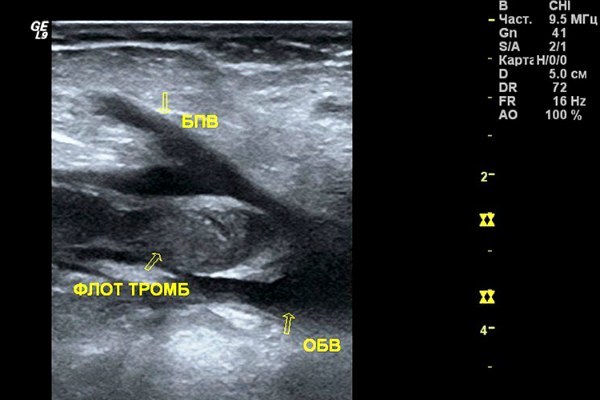

Образование тромбозов

Процесс образования тромбозов происходит прижизненно, при этом в просветах сосудов появляются кровяные сгустки, называемые тромбами.

Сужая сосудистый просвет, тромбы замедляют кровоток, следствием чего являются гипоксические и ишемические нарушения тканей.

Если тромб перекрывает больше 90% поперечного сечения сосуда, это чревато возможными инфарктами, сопровождаемыми некротической деформацией тканей.